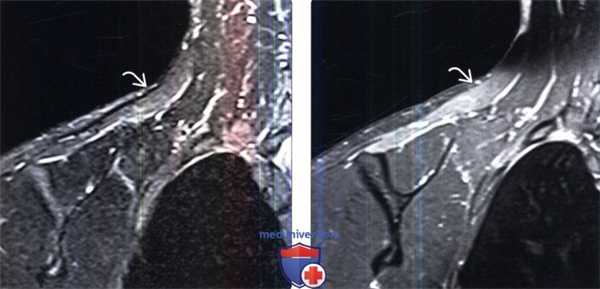

(Слева) На фронтальном STIR МР-И определяются признаки денервационного отека трапециевидной мышцы, иннервируемой спинальными корешками добавочного нерва. Этот нерв может быть травмирован при ношении на плече тяжелого груза.

(Справа) На фронтальном FS Т1-ВИ с КУ у этого же пациента отмечается равномерное контрастное усиление пораженной мышцы. Разрывы мышцы в отличие от подобной картины характеризуются неоднородной картиной.